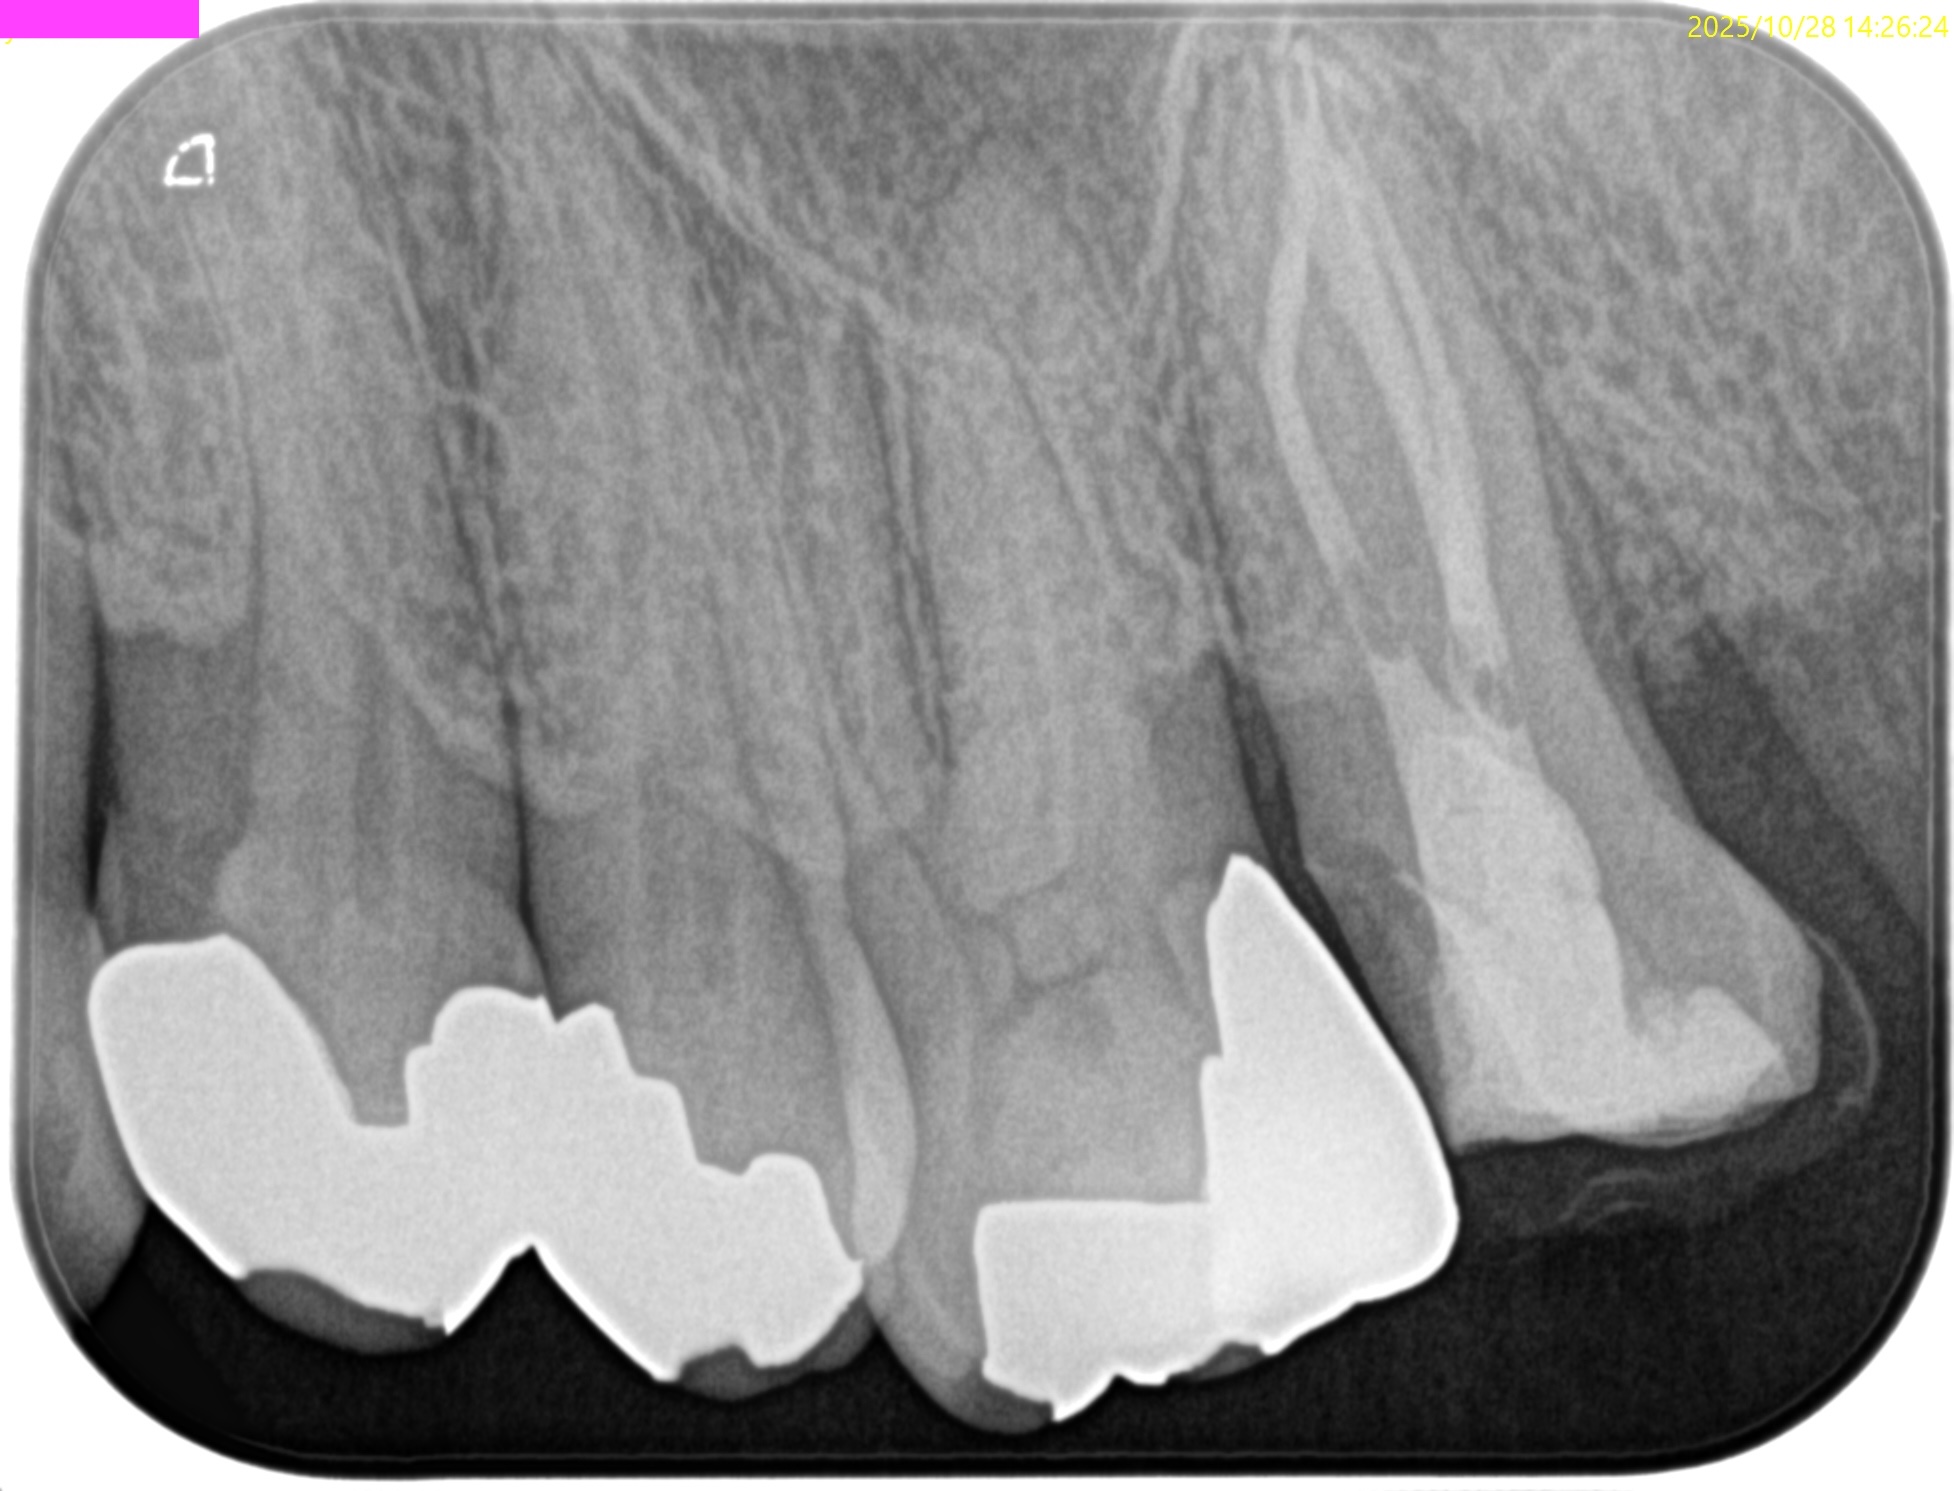

#15 RCT 1yr recall(2025.10.28)

MB

DB

P

初診時と比較した。

根尖病変、

術前の臨床症状、

術前の歯周ポケット

は完治した。

最終補綴もOKだ。

この日で経過観察も終診とさせていただいた。